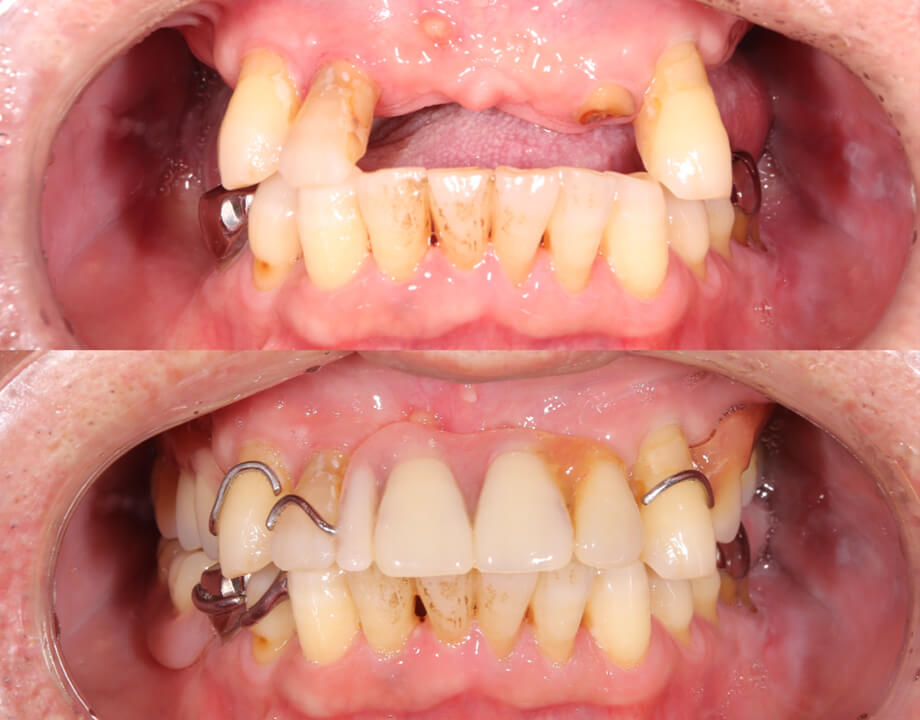

Case 07咬合再構成

アナログワックスアップ

→シュミレーション(ノーベルガイド)

→プロビジョナル(即時荷重)

→最終補綴物(ハイブリッドクラウン)